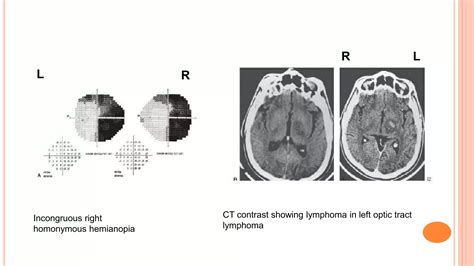

To grasp what happens in Left Homonymous Hemianopia, one must understand how the brain processes light. Signals from the retina travel through the optic nerves to the optic chiasm. Here, the nerve fibers cross. The fibers from the left side of each retina travel to the left side of the brain, while fibers from the right side of each retina travel to the right side of the brain. When an injury—such as a stroke, brain tumor, or traumatic brain injury—occurs in the right hemisphere of the brain (specifically the optic radiation or the visual cortex), the patient loses the ability to perceive the left side of their world.

Diagnosis typically begins with a comprehensive neurological exam followed by formal visual field testing. Doctors use perimetry—the gold standard for mapping the visual field—to pinpoint the exact boundaries of the scotoma (blind spot). Advanced imaging, such as an MRI or CT scan, is then utilized to locate the underlying brain lesion.